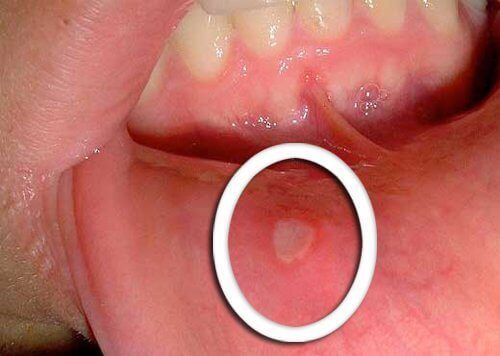

Το πρωιμότερο σύμπτωμα του στοματοφαρυγγικού καρκίνου είναι μικρές πληγές που δεν θεραπεύονται.

Συνήθως εμφανίζονται κόκκινες ή λευκές πληγές στη γλώσσα, στα ούλα ή στα χείλη. Προσέξετε κάθε ασυνήθιστη αλλαγή που δεν εξαφανίζεται σε μερικές μέρες και ενημερώστε τον γιατρό σας.